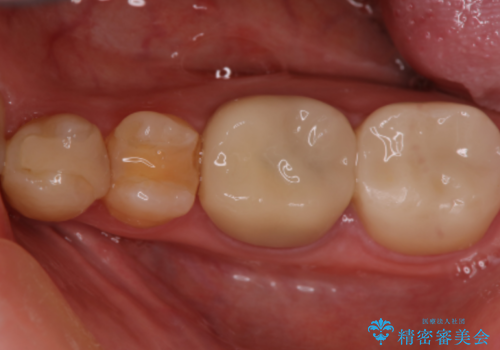

銀歯を外し、虫歯治療を行い、セラミックインレーにて治療しました。

銀歯を除去し、虫歯をとって、セラミックインレーにて治療を行いました。

- 7.7万円費用は治療当時の料金となります